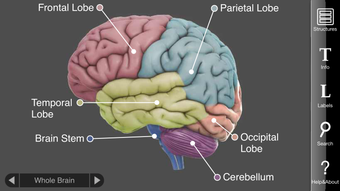

باستخدام شاشة اللمس، يمكن للمستخدمين تدوير وتكبير وتصغير 29 هيكلًا دماغيًا تفاعليًا. يوفر كل هيكل معلومات مفصلة حول وظائفه واضطراباته وأضرار الدماغ ودراسات الحالة وروابط للأبحاث الحديثة. تساعد هذه المعلومات الشاملة المستخدمين على فهم كيفية عمل كل منطقة في الدماغ وما يحدث عند إصابتها وكيف يتورط في الأمراض العقلية.

تم إنشاؤه بواسطة Vivid Apps و AXS Biomedical Animation Studio لمركز DNA Learning Center التابع لمختبر كولد سبرينغ هاربور، الدماغ ثلاثي الأبعاد هو أداة لا تقدر بثمن لأي شخص مهتم بعلم الأعصاب أو دراسة الدماغ البشري. سواء كنت طالبًا أو باحثًا أو مجرد فضولي بشأن الدماغ، يوفر هذا التطبيق تجربة مشوقة ومعلوماتية.